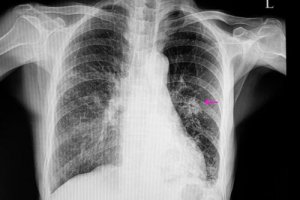

In such cases, the nodules will have an irregular appearance with poorly defined edges; this is visible in the x-ray. Also, they’re usually smaller than the benign ones. In addition, they’re part of certain risk factors, such as:

Once this is done, a doctor must perform certain imaging tests to locate the nodule. In addition, the images will allow them to observe certain characteristics such as shape and size. This is because they’re important for differentiating a benign nodule from a possibly malignant one.

The most common ways to diagnose them are via chest x-rays and computed tomographies. In order to find out the exact cause of a lung nodule, physicians also do biopsies sometimes, as these allow them to analyze the tissue.